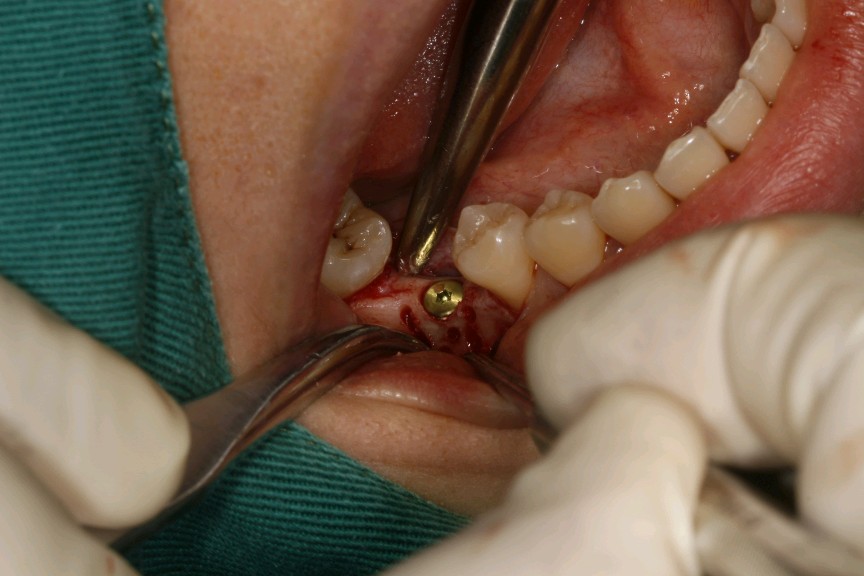

患者女,二十七岁,46牙体缺失近一年,牙槽崎吸收较多,粘膜无红肿、对合牙轻度伸长,邻牙轻微松动,龈周﹣。 x 示牙槽骨密度正常。告知患者治疗方案,患者选择种植修复。抽静脉血20ml,制作 CGF ,植Nobel Pcc 种植体4.3*10mm,上覆盖帽,颊侧骨缺损区植入 bio - oss 骨粉0.25g及 CGF ,盖 bio - Gide 膜及 CGF 膜,严密缝合。直至今日戴牙,咬合适宜,患者满意。